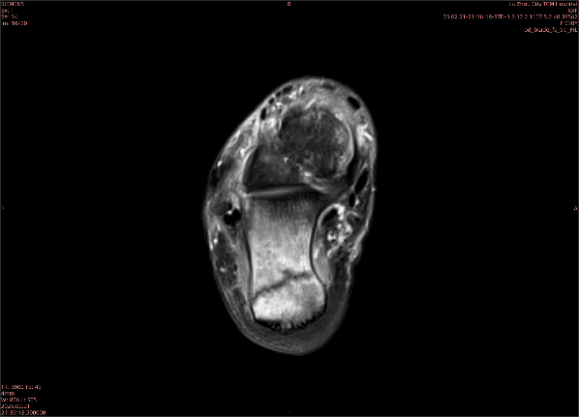

隱性骨折在MRI表現(xiàn)為T1WI序列上見由關(guān)節(jié)面向骨干走行的形態(tài)各異低信號(hào)區(qū),有線狀、條狀、紊亂低信號(hào),信號(hào)強(qiáng)度不均勻。與T1WI低信號(hào)改變相對(duì)應(yīng)部位在T2WI上表現(xiàn)為相應(yīng)形狀的高、低混雜信號(hào),且部分低信號(hào)周圍可見高信號(hào)水腫改變。STIR序列圖像上病灶呈顯著高信號(hào),與信號(hào)被抑制的臨近正常骨髓形成鮮明對(duì)比,分界也較T2WI成像更為清楚。脂肪組織抑制技術(shù)是MRI的一個(gè)重要性能,脂肪抑制技術(shù)在MRI應(yīng)用中可以改善組織對(duì)比和增加病變顯示機(jī)會(huì),這樣骨髓的脂肪抑制后就不會(huì)有任何信號(hào),而隱性骨折線及骨髓水腫的異常高信號(hào)就會(huì)更加明顯的顯示出來。

舉例圖像

圖1

專業(yè)解釋看不懂沒關(guān)系,大家看圖1和圖2就可以了,這是同一個(gè)患者跟骨的磁共振和CT圖像,圖1的紅色箭頭指示的黑線就是磁共振圖像顯示的骨折線,一目了然。而對(duì)比圖2的CT圖像上并未顯示異常。